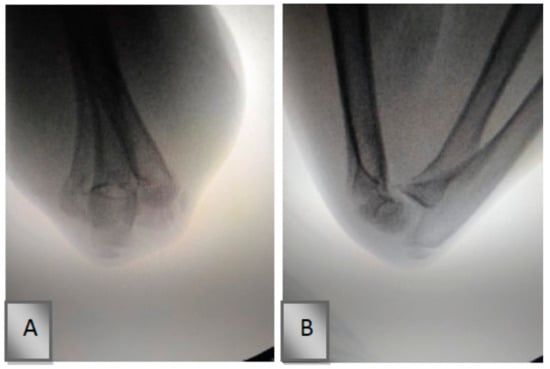

2.1. Surgical Technique